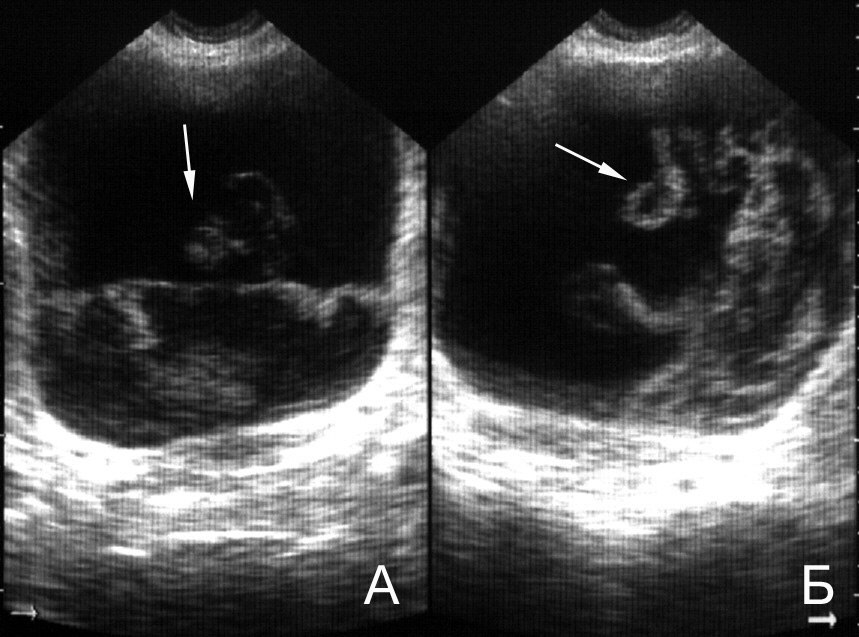

Ультразвуковое исследование не является методом выбора в диагностике хронического цистита, так как сонографическая картина мочевого пузыря при цистите мало чем отличается от нормальной. Признаком выраженного воспаления мочевого пузыря может быть утолщение его стенок в наполненном состоянии более 5 мм и позыв на мочеиспускание при его сравнительно малом объеме. На наличие цистита может указывать мелкодисперсная эхогенная взвесь в мочевом пузыре (рис. 8,14,16,17), обусловленная высоким цитозом мочи [7, 50].

Рис. 16. Мочевой пузырь при цистите, лейкоцитурии. Определяется горизонтальный уровень нежной эхоструктуры (обозначен стрелкой), изменяющий свою форму и локализацию при перемене положения тела. (Поперечное сканирование, А − в положении пациента на спине, Б − на левом боку. Конвексный датчик 5 МГц, “Logiq-500”).

Рис. 17. Мочевой пузырь при цистите, пиурии. Вязкий гной образует причудливые фигуры на дне пузыря, при изменении положения тела он медленно перемещается, почти не меняя формы. (Поперечное сканирование, А − в положении пациента на спине, Б − на левом боку. Конвексный датчик 5 МГц, “Logiq-500”).